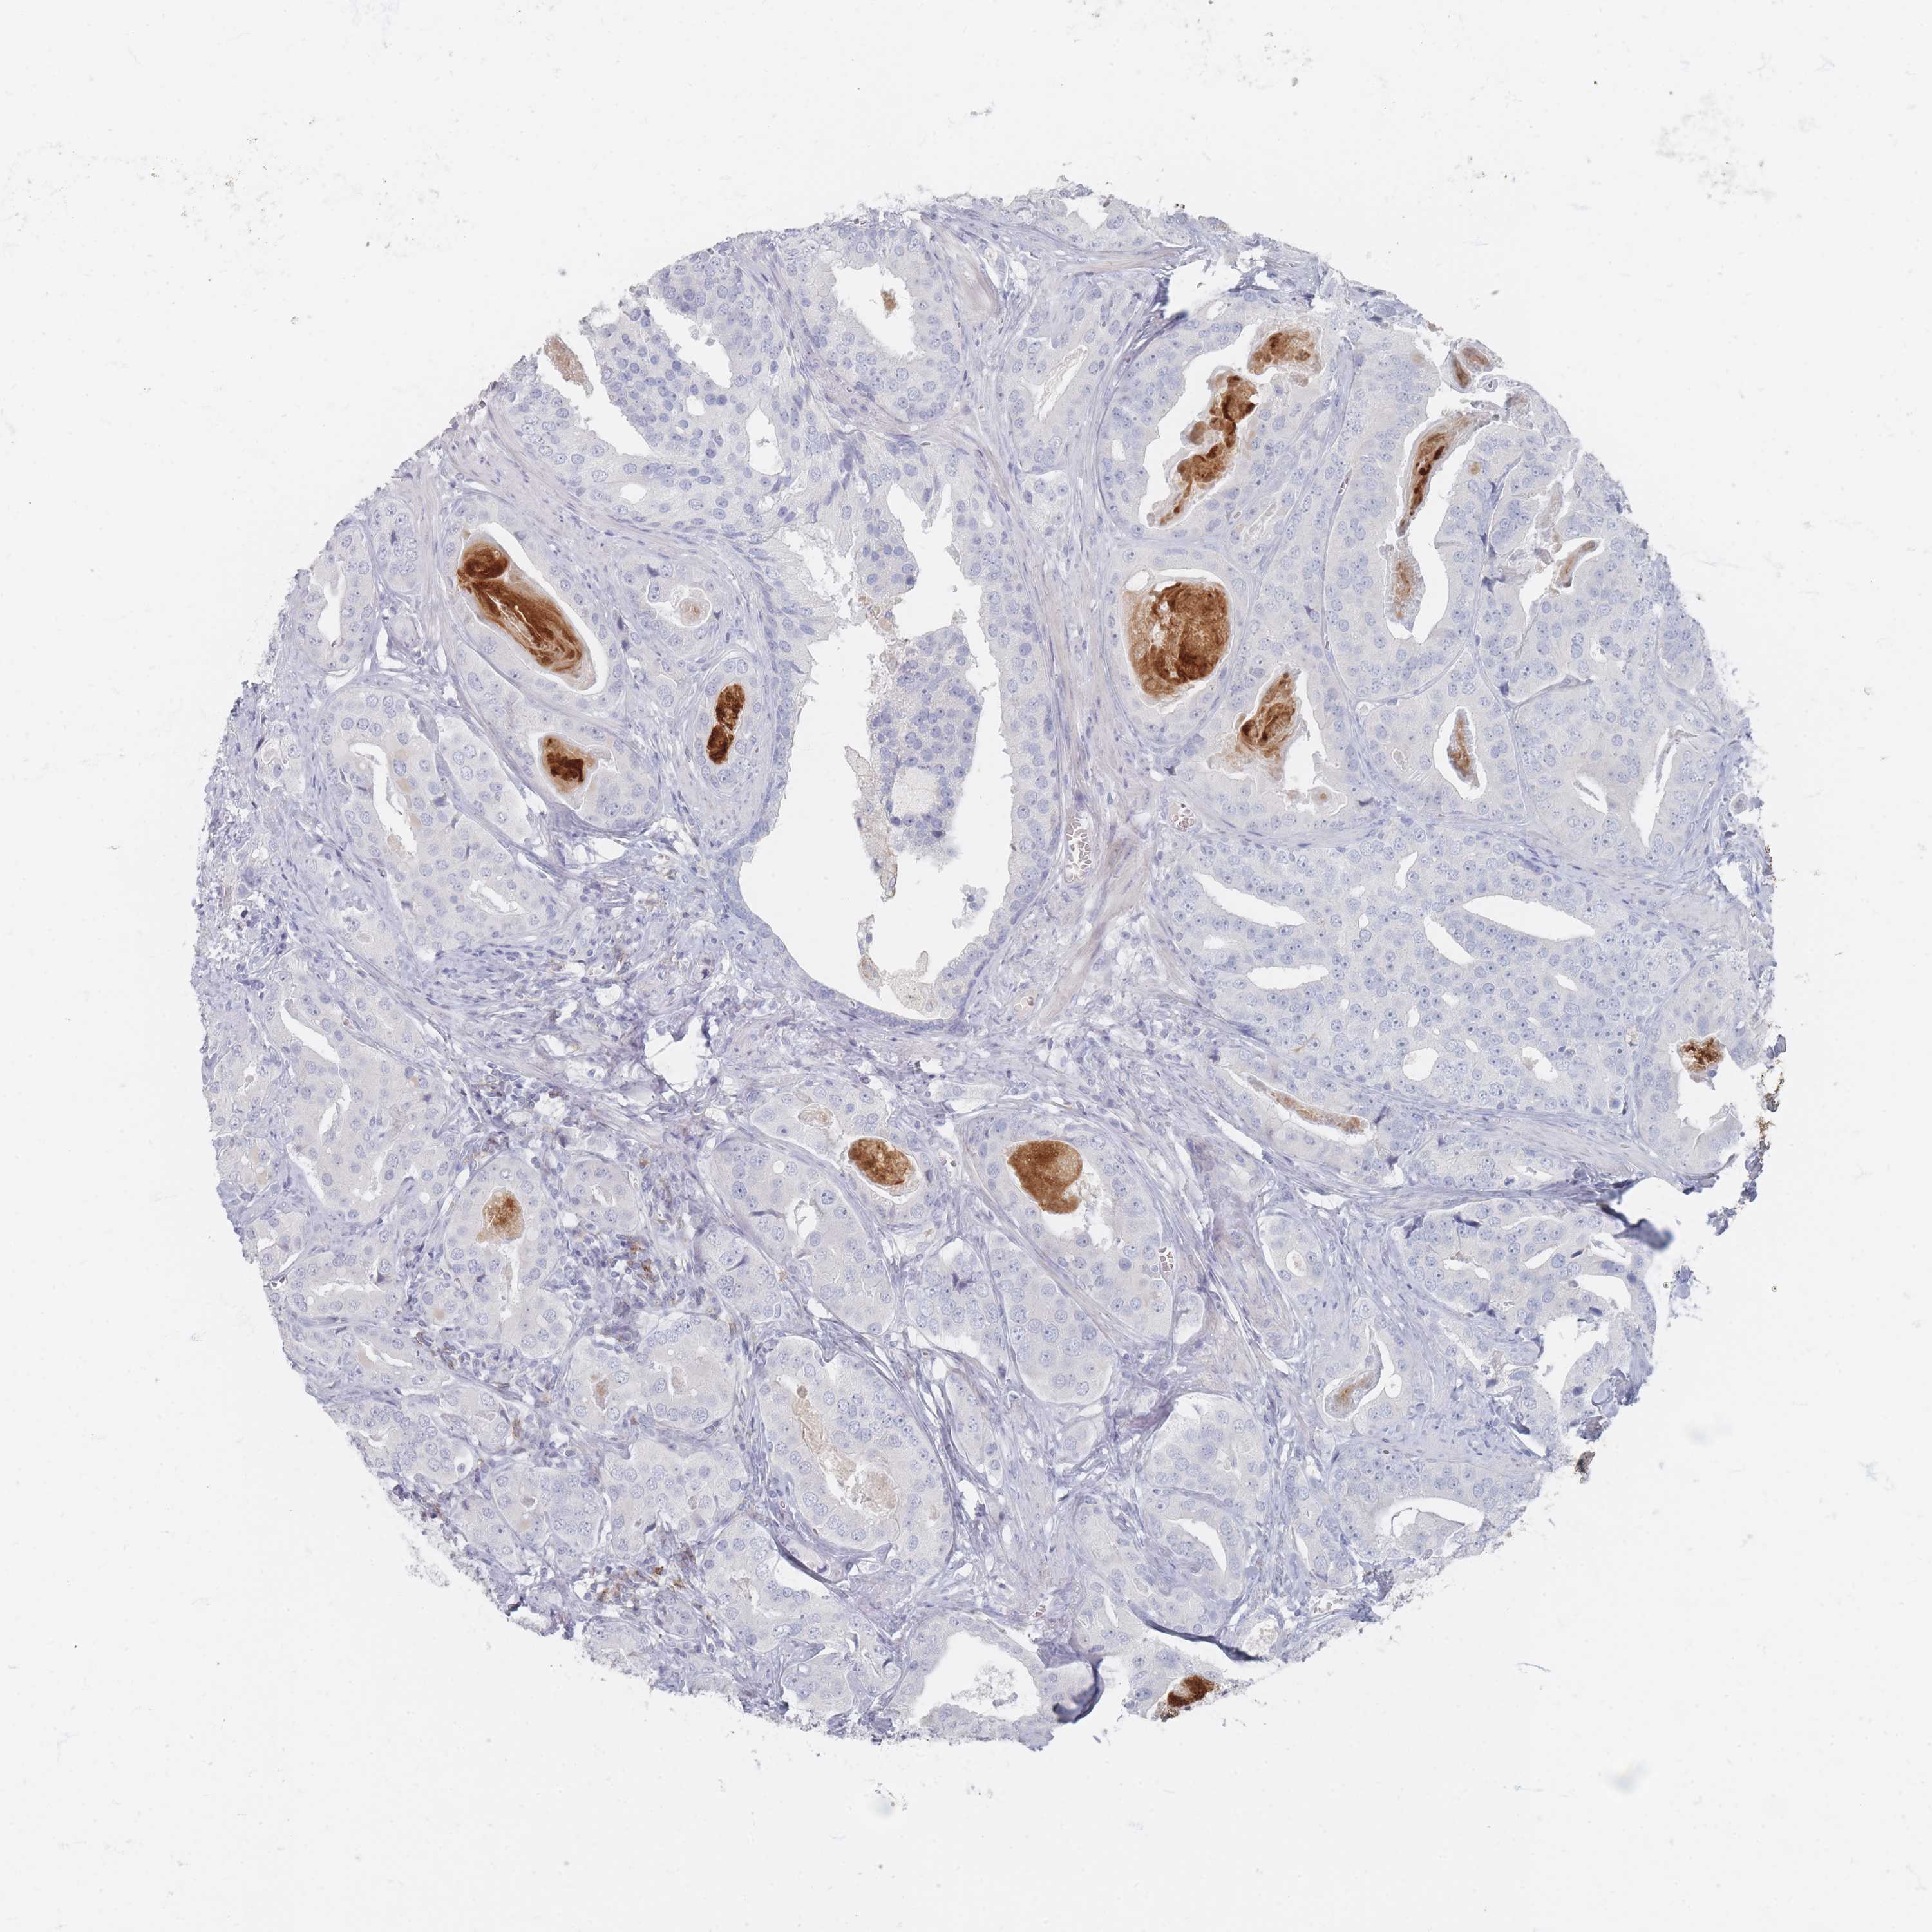

PROSTATE CANCER - Protein expressioni

A mouse-over function shows sample information and annotation data. Click on an image to view it in a full screen mode. Samples can be filtered based on level of antibody staining by selecting one or several of the following categories: high, medium, low and not detected. The assay and annotation is described here.

Note that samples used for immunohistochemistry by the Human Protein Atlas do not correspond to samples in the TCGA dataset.

Antibody stainingi

Antibody staining in the annotated cell types in the current human tissue is reported as not detected, low, medium, or high, based on conventional immunohistochemistry profiling in selected tissues. This score is based on the combination of the staining intensity and fraction of stained cells.

Each image is clickable and will lead to virtual microscopy that enables deeper exploration of all samples and also displays staining intensity scores, fraction scores and subcellular localization as well as patient and tissue information for each sample.

Antibody HPA032120

Antibody HPA032121

Antibody CAB002492

Staining

High

Medium

Low

Not detected

Intensity

Strong

Moderate

Weak

Negative

Quantity

>75%

75%-25%

<25%

None

Location

Nuclear

Cytoplasmic/membranous

Cytoplasmic/membranous,nuclear

Adenocarcinoma, High grade

Adenocarcinoma, Low grade

Adenocarcinoma, Medium grade